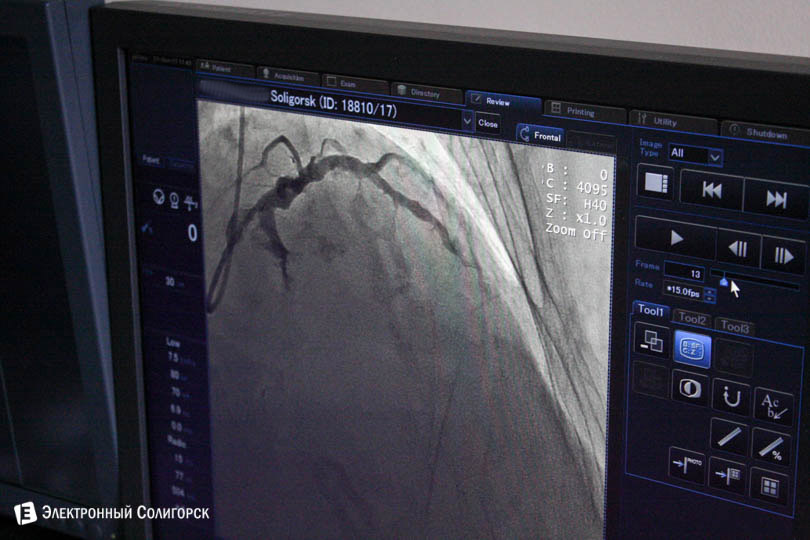

Ангиограф появился в Солигорске в 2014 году. Про него много писали, но если кто не помнит – это аппарат последнего поколения, высокоточный, который позволяет врачам видеть сосуды. Благодаря ему они точно диагностируют болезни сосудов и делают безболезненные операции. На тот момент ни в одной районной больнице Беларуси такого аппарата не было, но сейчас ангиограф есть и в Барановичах. Мы узнали, как сейчас работает кабинет и что с ним произошло за эти три года.

Врачи обезбаливают только место, куда вводят иглу. Чаще всего иглу вводят в запястье или в складку между бедром и пахом. "Пациент всё время в сознании, мы с ним разговариваем. Если кто-то захочет, может на мониторе увидеть, что у него происходит внутри", - рассказывает Александр.

Фото Александра Януковича